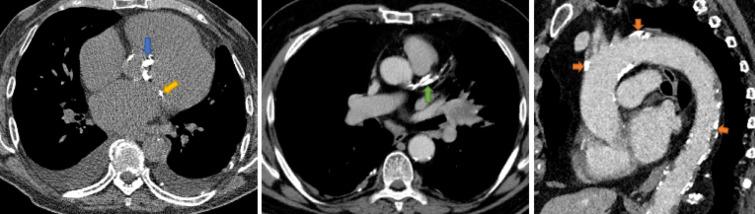

Coronary and cardiac calcification are frequent incidental findings on non-gated thoracic computed tomography (CT). However, radiologist opinions and practices regarding the reporting of incidental calcification are poorly understood.

The survey was completed by 200 respondents: 10% trainees and 90% consultants. Calcification was not reported by 11% for the coronary arteries, 22% for the aortic valve, 35% for the mitral valve and 37% for the thoracic aorta. Those who did not subspecialise in cardiac imaging were less likely to report coronary artery calcification ( = 0.005), aortic valve calcification ( = 0.001) or mitral valve calcification ( = 0.008), but there was no difference in the reporting of thoracic aorta calcification. Those who did not subspecialise in cardiac imaging were also less likely to provide management recommendations for coronary artery calcification ( < 0.001) or recommend echocardiography for aortic valve calcification ( < 0.001), but there was no difference for mitral valve or thoracic aorta recommendations.

Incidental coronary artery, valvular and aorta calcification are frequently not reported on thoracic CT and there are differences in reporting practices based on subspeciality.

On routine thoracic CT, 11% of radiologists do not report coronary artery calcification. Radiologist reporting practices vary depending on subspeciality but not level of training.